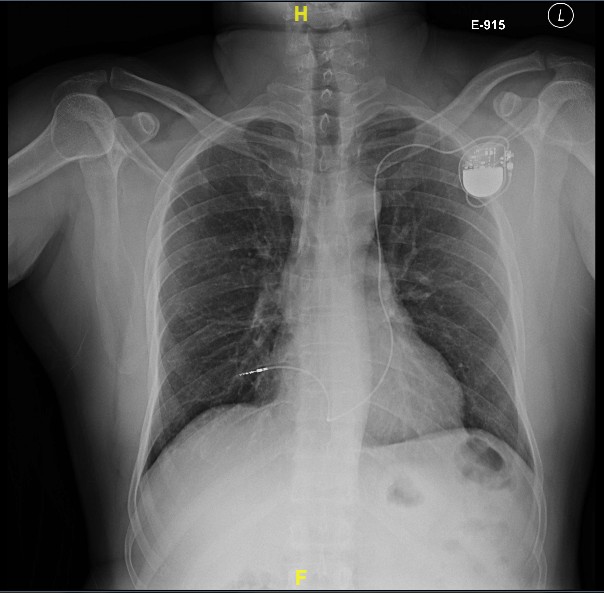

Post implant

Post procedure care

• Immobilisation / bed rest ?

• Analgesia

• Chest X ray after 4-6 hours

• ECG / Pacemaker check

• Antibiotics ?

• Shower ?

Post procedure CXR

pneumothorax_post_ppm.jpg